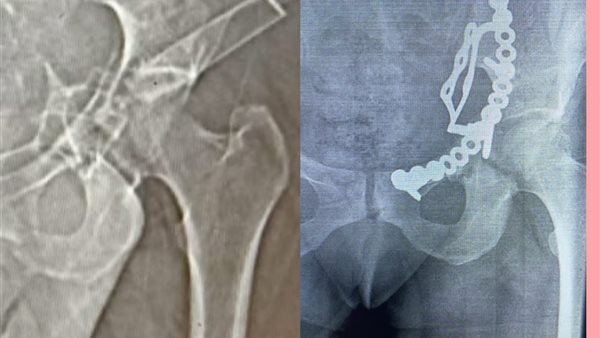

وأوضح وكيل الوزارة، في بيانٍ له، قبل قليل، أنه تم إجراء عملية إصلاح الكسور المتعددة المفتتة بعظام الحوض للسيدة تحت إشراف مدير مستشفى أبو حماد المركزي، إذ تم إجراء عملية رد مفتوح مع تثبيت داخلي لكسر مفتت بالحق الحرقفي لـ عظم الحوض للسيدة، وذلك من خلال جراحة فتح البطن والحوض باستخدام شريحة من نوع خاص تحت مُخدر عام بغرفة العمليات بمستشفى أبو حماد المركزي.

وأشار وكيل وزارة الصحة بمحافظة الشرقية، إلى أن العملية التي أجريت تُعد ذات طابع خاص، وذلك بعد دخول المريضة قسم الاستقبال والطوارئ بمستشفى أبو حماد المركزي، إثر ادعاء حادث مروري، منوهًا بأنه تم إجراء كافة الفحوصات اللازمة، وتبين إصابة المريضة بجرح بالمثانة نتج عنه بول دموي ووجود كسر مفتت بالحق الحرقفي لعظم الحوض، قبل أن يشير إلى إجراء العملية، وأن المريضة الآن في حالة جيدة ومستقرة تحت متابعة الأطباء بمستشفى أبو حماد المركزي.